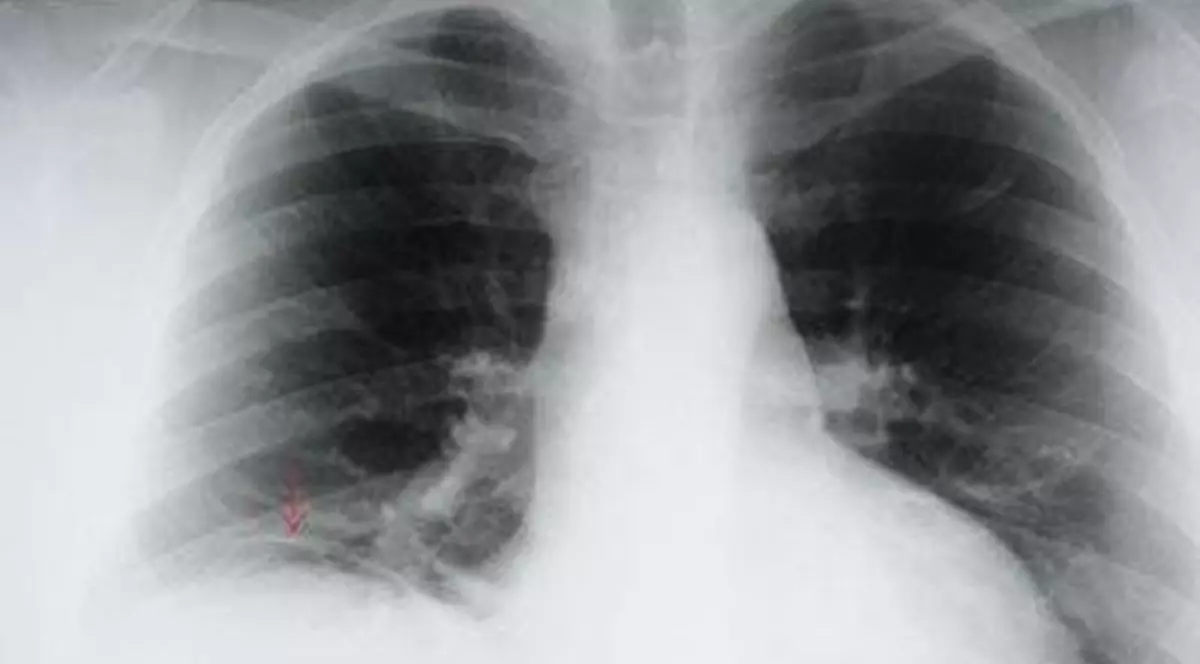

Acest tip de cancer care atacă plămânii se diagnostichează cu dificultate şi adesea, la momentul descoperirii, este deja în stadiu metastazat. Este posibil ca tumora din plămân să nu determine niciun simptom în regiunea pieptului, însă ea se poate însoţi de alte semne care vă determină să vă adresati medicului. Este bine să rugaţi doctorul să vă facă o radiografie dacă aveţi în mod repetat următoarele simptome: tuse, • spută cu sange, dificultate în a respira, o durere, pneumonii sau bronşite repetate, oboseală, lipsa poftei de mâncare şi scădere în greutate, răguşeală sau transpiraţii ale feţei şi gâtului.